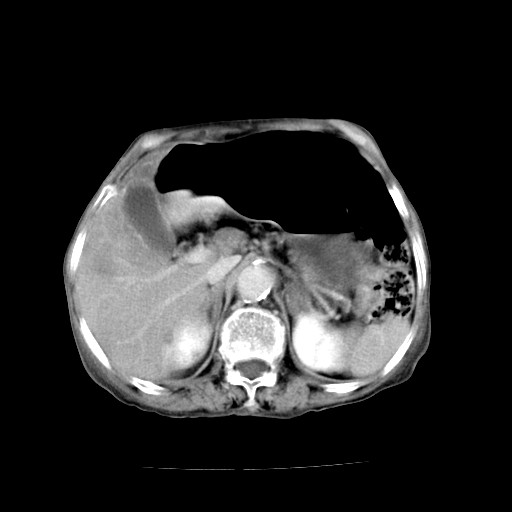

标题: CT19149:女,68岁,腹胀、恶心两周。 [打印本页]

标题: CT19149:女,68岁,腹胀、恶心两周。

女,68岁,腹胀、恶心两周,先做ct平扫,当时家属不同意强化,6天后家属要求增强扫描。

考虑肝癌。

1、胃窦癌; 2、局灶性脂肪肝。

1、胃窦癌?建议行胃镜!; 2、局灶性脂肪肝。

1.局灶性脂肪肝;2.胃窦癌可能,建议行进一步检查。

1)不排除胃窦癌;建议行胃镜检查。 2)局灶性脂肪肝。

1)不排除胃窦癌;建议行胃镜检查。 2)局灶性脂肪肝。腹水。

考虑:胃窦ca,腹水,脂肪肝

1)胃窦壁厚,考虑胃窦癌?建议行胃镜检查。 2)局灶性脂肪肝。

支持考虑1、胃窦癌?建议行胃镜!; 2、局灶性脂肪肝。  3、双侧胸腔积液,胸膜增厚

不均匀脂肪肝,胃腔改变须结合钡餐或胃镜观察

1)局灶性脂肪肝。2)胃窦癌可能,建议行胃镜检查。